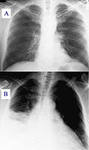

Чаще всего пневмония возникает как результат запущенного бронхита или вследствие снижения активности иммунной системы. Пневмония может начинаться по-разному, что часто сбивает больного с толку, заставляя предположить иные заболевания. В результате пневмония развивается незаметно, переходя в сложные и запущенные формы.

Пневмония может протекать латентно, с периодическими обострениями. Это характерно для хронической...